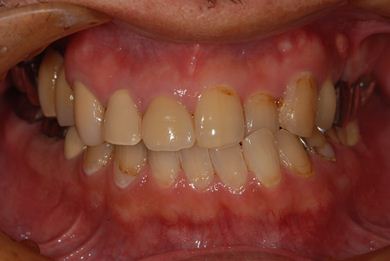

インプラントの症例写真 IMPLANT

インプラント治療

| 治療方針 | 左下欠損部分をインプラント治療にて機能的・審美的回復を行う。 | ||||||||||||||||||||||||||||||||

| 治療内容 | インプラント2本、ハイブリッドセラミッククラウン2本 | ||||||||||||||||||||||||||||||||

| 総治療費 | 399,000円 | ||||||||||||||||||||||||||||||||

| 治療期間 | 9ヶ月 |